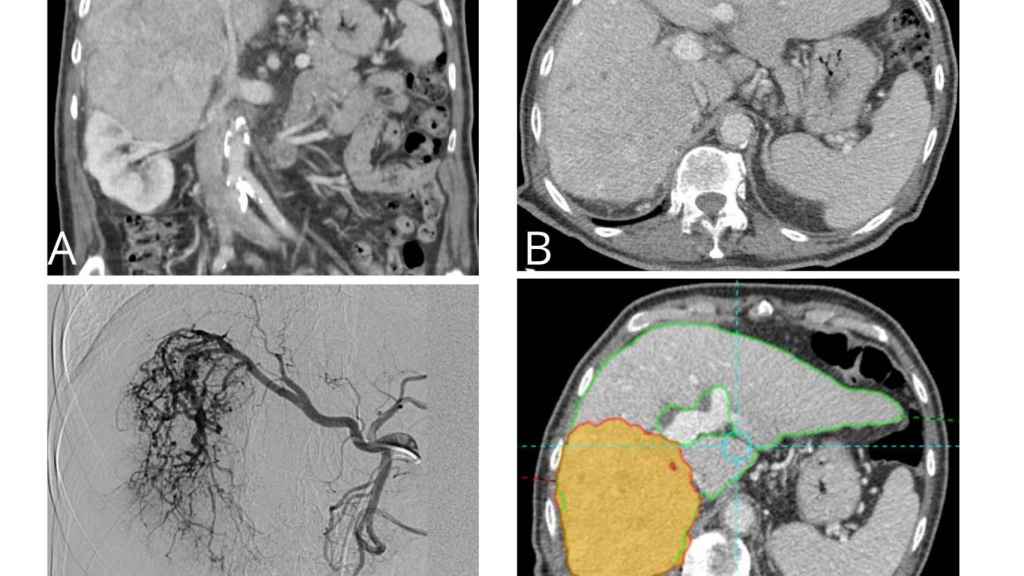

La radioembolización es una terapia que, a través de microesferas radiactivas, inciden en el cáncer y mejoran la supervivencia y calidad de vida en los pacientes con esta patología con hepatocarcinoma, colangiocarcinoma y metástasis de tumores colon-rectales.

“La radioembolización es una terapia dirigida que consiste en que millones de microesferas de cristal radioactivas con itrio-90 producen una ablación intravascular en el lecho de la lesión”, matiza el doctor, quien indica que “estas microesferas del grosor de un cabello humano se dirigen directamente al tumor hepático a través de la arteria hepática, donde se introducen por medio de un catéter”.

“Las microesferas fluyen directamente hacia el tumor a través de los vasos sanguíneos del propio cáncer y se alojan permanentemente en el mismo y debido a que el procedimiento incide directamente en el tumor, la radiación destruye las células del cáncer con un impacto mínimo sobre el tejido hepático normal adyacente”, afirma.